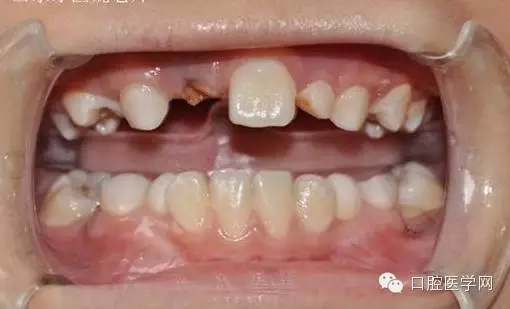

基本資料:男8歲、祖籍山東滕州、二年級(jí)。

主訴:門牙遲遲不長

現(xiàn)病史:右乳上一牙根滯留。

小兒8歲發(fā)現(xiàn)右上門牙遲萌,右乳一殘根。

用時(shí)9周完成埋伏牙牽引。

孩子自信的微笑,是我們最大的幸福。